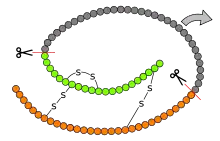

Some prohormones contain structures other than inactive peptide hormones for the purpose of keeping hormone expression suppressed. For example, proinsulin contains an extra non-hormonal chain called C-peptide that binds two insulin peptide chains together, designed to keep both chains inactive by binding to their ends, specifically, their C-domain junctions, which have been proposed to be their site of binding to hormone-expression receptors in the cell.[9] Despite the restrictions it enables, the C-peptide folds the proinsulin chains to make their junction ends accessible to be cleaved by prohormone convertases later, making the folding of the proinsulin chain containing C-peptide essential for the proper cleavage of proinsulin to successfully produce insulin.[10]

The main regulator of prohormone to hormone conversion is prohormone convertase. Located in the Golgi apparatus, it uses endoproteolytic cleavage to separate peptide hormones from each other and removes extended amino acid residues that hinder the inactive peptides from being active proteins.[4] Because of this role, prohormone convertase is one of the deciding factors for regulation of hormone content in the body, as it has the ability to change an inactive protein with unsubstantial hormonal effect on the body, to a fully active protein with a meaningful hormonal effect.[4][13]

For peptide hormones, the conversion process from prohormone to hormone (pro-protein to protein) typically occurs after being exported to the endoplasmic reticulum and often requires multiple processing enzymes.[14] Proamylin, which is cosecreted with proinsulin, requires the above three factors and an amidating monooxygenase to convert itself to an active hormone.[15] Some pro-protein precursors, such as preproinsulin, also go through this process, with the added step of removing a signal peptide by signal peptidases, to convert said precursors into prohormones.[14]